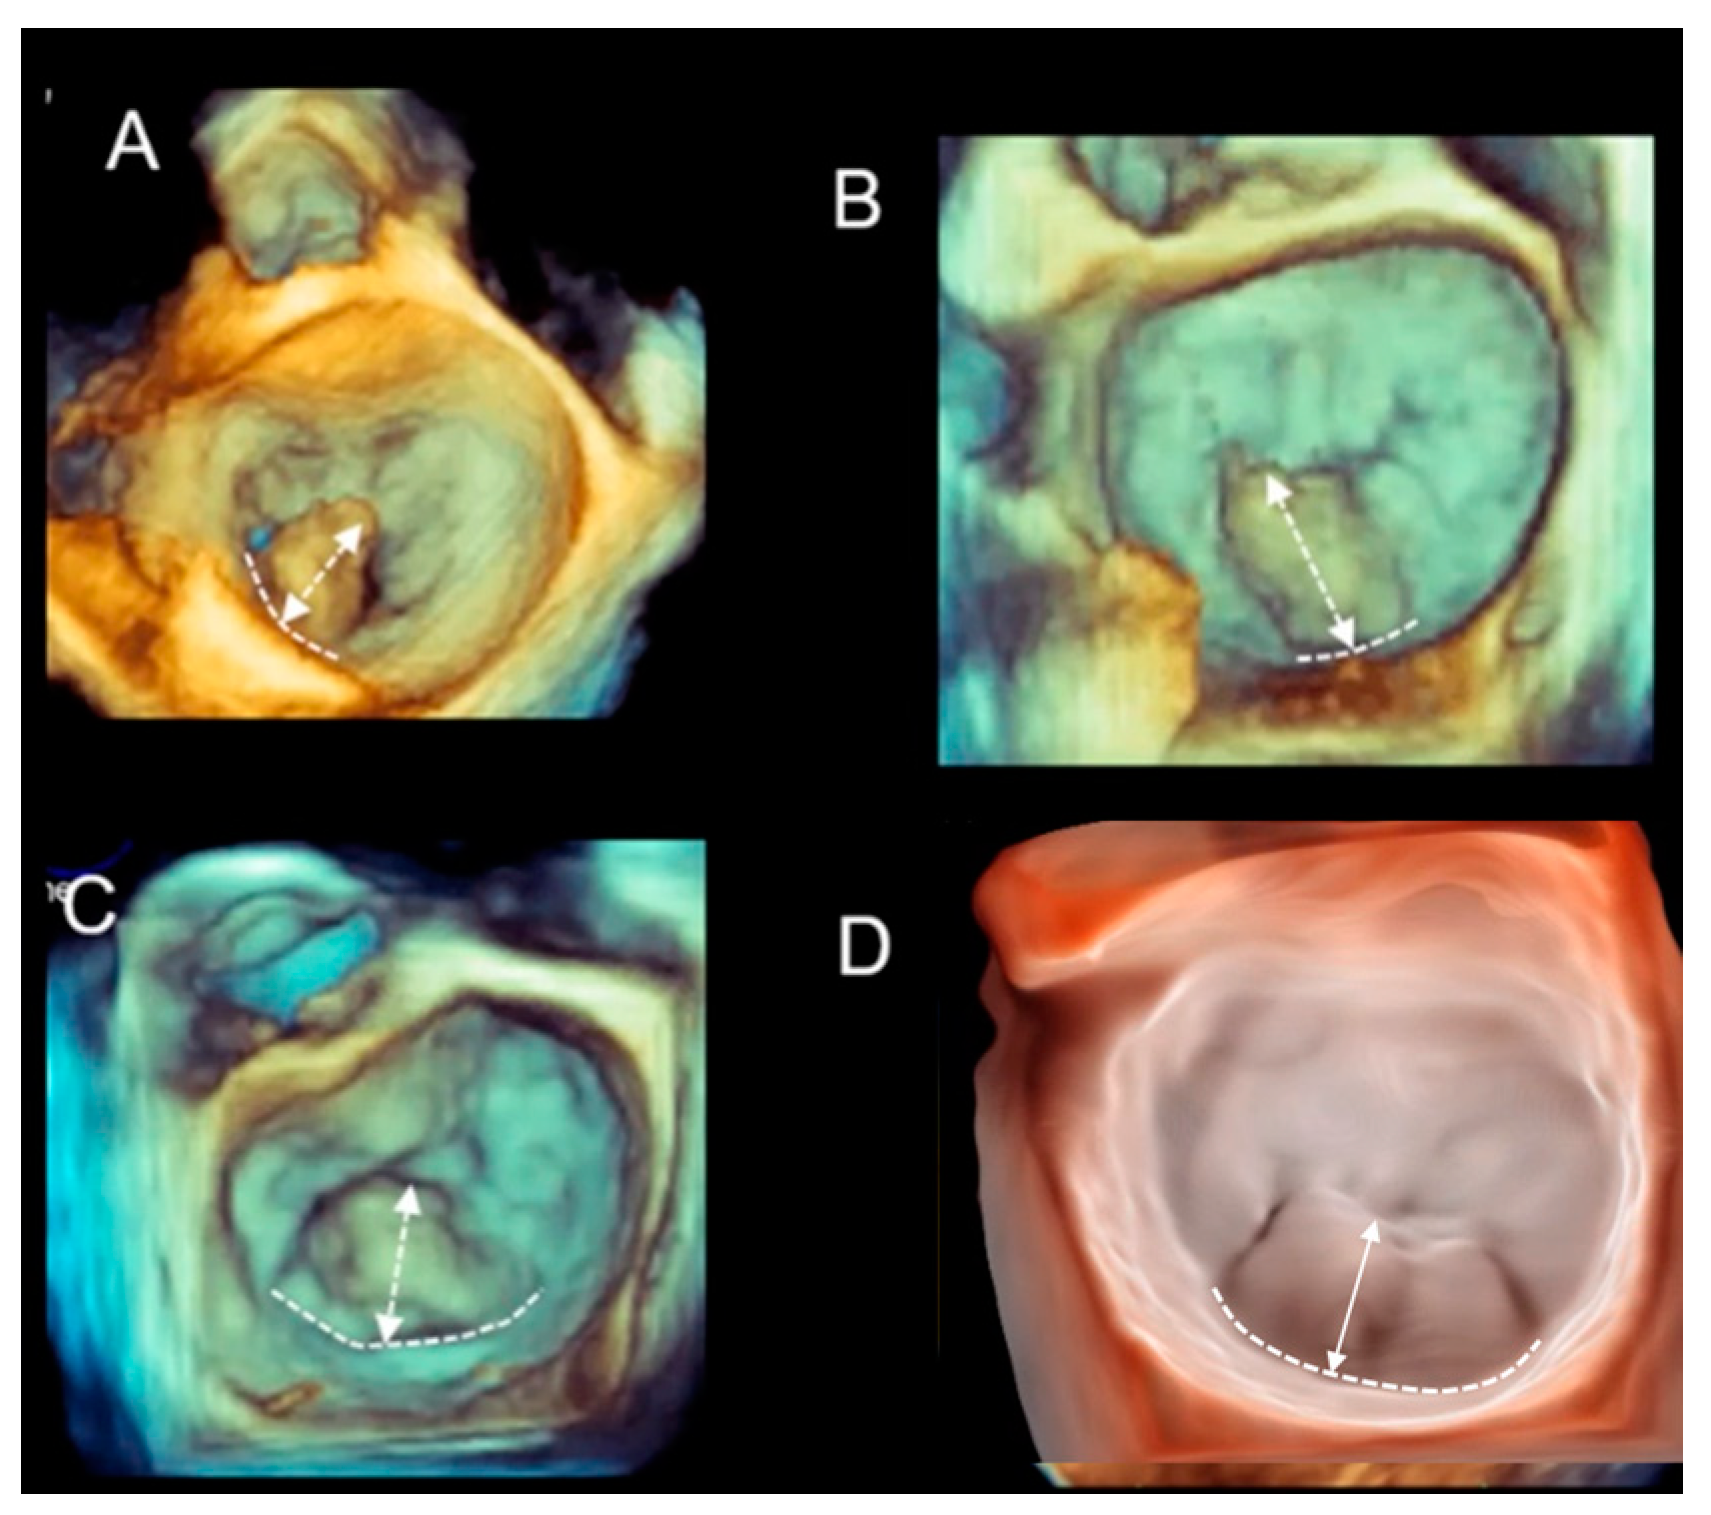

Different Shapes of P2 Prolapse, Partial Prolapse, and Commissural Prolapse

| Phenotype | Description | Image |

|---|---|---|

| Fibroelastic deficiency | This phenotype is characterized by a deficient production of collagen, elastin, and proteoglycans. Leaflets preserve their own three-layer arrangement, but upon surgical inspection, they appear fragile and translucent. The etiology of connective tissue deficiency in FED is unknown, but it has been suggested that it may be the result of an accelerated ageing process. The cause of regurgitation is the rupture of one or more primary chordae tendineae, which usually involves a single scallop. The figure shows a small P2 prolapse in an otherwise apparently normal MV. |  |

| Fibroelastic deficiency plus | This phenotype is characterized by a single scallop prolapse, but the involved scallop is redundant and affected by myxomatous degeneration. The remaining scallops are normal. Qualitative histological lesions in the prolapsed tissue of FED plus are similar to those of Barlow’s disease. It has been suggested that FED plus may be considered a sort of worsening stage of FED, leading to the hypothesis that the myxomatous changes could also be secondary to jet lesions. The figure shows a large P2 prolapse with ruptured chordae tendineae (arrows). |  |

| Forme fruste | In this phenotype, the entire posterior leaflet is redundant and is affected by myxomatous degeneration, while the anterior leaflet is macroscopically and histologically normal. It can be speculated that this phenotype is an incomplete form of Barlow’s disease. The figure shows multiple prolapses (asterisks) of the posterior leaflet. |  |

| Barlow’s disease | Barlow’s disease is the result of an abnormal accumulation of myxomatous substances (mainly proteoglycans) in the spongiosa layer, and a simultaneous disruption of collagen fibers in the fibrosa layer. As a consequence, the three-layered arrangement of the leaflets is lost. The characteristic macroscopic appearance, either in pathological specimens or in the operating room, is that of a thick, bulky, redundant leaflet, elongated chordae tendineae, and annular dilatation. The excess leaflet tissue leads to the displacement of both leaflets beyond the annulus, with a lack of coaptation and consequent MR. The figure shows an example of Barlow’s disease seen from a tangential view largely protruding into the left atrium. LAA = left atrial appendage, AML = anterior mitral leaflet; PML = posterior mitral leaflet. |  |